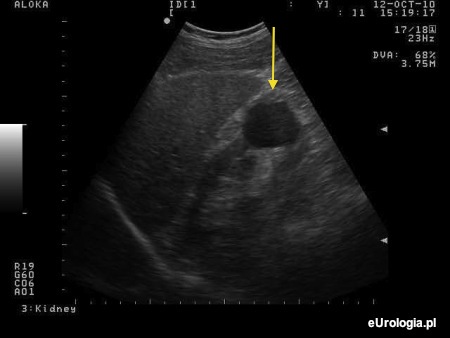

Fot. Obraz USG torbieli dolnego bieguna prawej nerki.

W okolicy dolenego bieguna nerki prawej w badaniu USG mam opisywane dwie torbiele wielkości 1 i 2 centymetrów. We wnioskach z badania USG mam napisane: Torbiele proste nerki prawej. Czy takie torbiele wymagają jakiegoś leczenia tabletkami lub operacyjnego? Radiolog na moje pytanie odpowiedział, że taka jest uroda nerki.

Torbiele proste o takich rozmiarach w okolicy dolnego bieguna nerki nie wymagają leczenia. W zupełności wystarczy coroczna kontrola w badaniu USG jamy brzusznej.